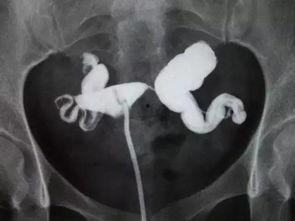

接下来,让我们来看看这个手术是怎么进行的。这里,我找到了一些专业的手术视频,可以让你更直观地了解整个过程。

为了让你更直观地了解手术过程,我找到了一些输卵管积水手术的视频。这些视频都是真实案例,你可以看到医生是如何操作的。

1. 手术开始:医生首先将腹腔镜插入你的腹部,然后通过摄像头观察输卵管的情况。

2. 找到积水部位:医生会仔细寻找积水的地方,并用工具将其清除。